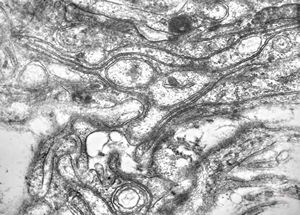

M,15y. | neurinoma n. optici